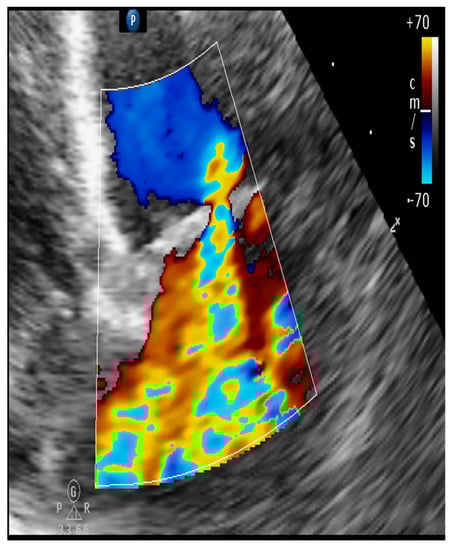

4.8.1. Evaluation of the Regurgitant Area

| Color flow imaging of the mitral regurgitation jet area | The most commonly used technique for assessing severity in dogs. The former method is not used in humans as it is not considered reliable for determining the severity of mitral insufficiency. |